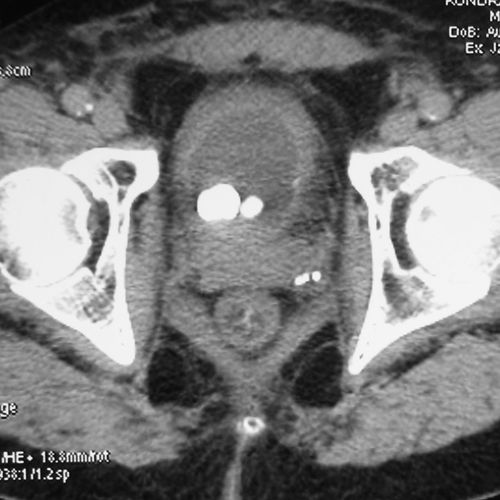

Лучевой цистит с исходом в микроцистис (цистпростатэктомия)